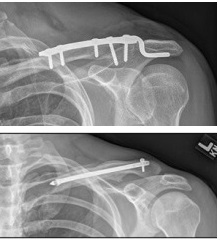

If surgery is required, the surgeon will realign the collarbone fragments and fix them together with either:

Metal Plate: A specially shaped metal plate, made of titanium or steel is placed over the top of the collarbone or occasionally around the front to hold the bones in the correct alignment. It is fastened in place with screws.

Intramedullary Fixation: A nail or rod may be used to fix the bone together. This goes through the middle of the bone (known as the canal) to hold the pieces together.

Whichever surgical method is used, you will normally be discharged home later that day or the following day. In most cases, the metal work will be left in place indefinitely, but if it starts to causes a problem, such as shoulder pain, stiffness or it shifts out of position, it can be removed once the collar bone has fully healed.